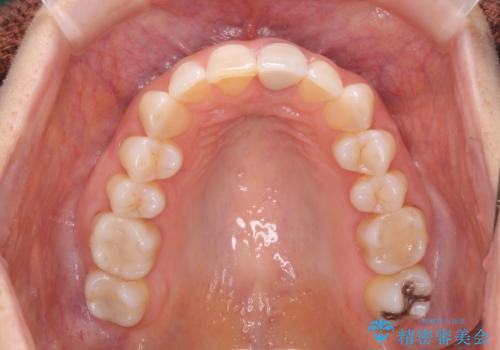

夜中の歯ぎしり ナイトガードで予防

- 20代女性

- 1ヶ月

- 2-5回

- 夜中の歯ぎしりをどうにかしたいとのことで来院されました。

ナイトガードを作成し歯ぎしりによる歯のすり減りを予防していきます。

- ナイトガード 33,000円費用は治療当時の料金となります

患者様ごとのナイトガードをオーダーメイドで作ることで、適合がよく咬合圧も分散させることができるようになります。